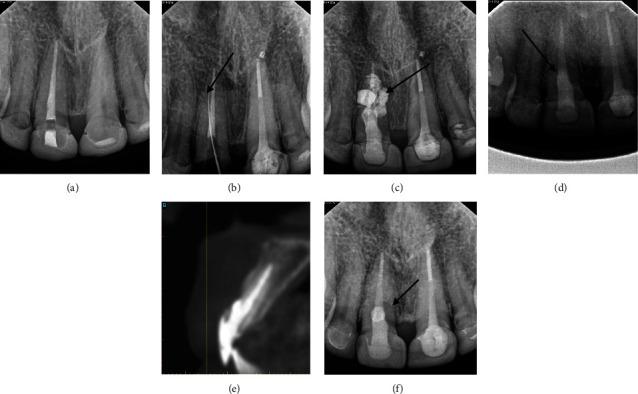

Iatrogenic root perforation presents a significant management challenge for clinicians as it may seriously harm the periodontium. More specifically, perforations occurring relative to the crestal bone have a poor prognosis even after repair due to their proximity to the gingival tissues. The current literature reports the use of various materials for root perforation repair including calcium hydroxide, glass ionomer cement, amalgam, and mineral trioxide aggregate (MTA), to name a few. This case report describes the clinical management of a cervical perforation that occurred on the maxillary central incisor. The perforated area was initially repaired with MTA but failed after one year, which resulted in an active lesion at the midlabial aspect of the tooth. The case was subsequently treated using a resin-modified glass ionomer cement (Geristore®) and deepithelialized free gingival graft (DGG). There were favorable clinical and radiographic outcomes at 1-, 3-, and 5-year follow-up. The use of DGG, however, led to some late complications such as gingival cul-de-sac and color discrepancy, which were later resolved with gingivoplasty and frenectomy. We thus conclude that Geristore® has the potential to be a better repair material than the existing ones for crestal and subcrestal root perforations.

医源性牙根穿孔给临床医生带来了重大的治疗挑战,因为它可能会严重损害牙周组织。更具体地说,相对于牙槽嵴顶骨发生的穿孔,即使在修复后预后也很差,因为它们靠近牙龈组织。目前的文献报道了使用多种材料进行牙根穿孔修复,包括氢氧化钙、玻璃离子水门汀、汞合金和三氧化矿物凝聚体(MTA)等等。本病例报告描述了上颌中切牙发生的颈部穿孔的临床治疗情况。穿孔区域最初用MTA修复,但一年后失败,导致牙齿唇面中部出现活动性病变。该病例随后使用树脂改性玻璃离子水门汀(Geristore®)和去上皮游离龈瓣(DGG)进行治疗。在1年、3年和5年的随访中,临床和影像学结果良好。然而,DGG的使用导致了一些晚期并发症,如牙龈盲袋和颜色差异,后来通过牙龈成形术和系带切除术得到了解决。因此,我们得出结论,对于牙槽嵴顶和牙槽嵴下牙根穿孔,Geristore®有可能成为比现有材料更好的修复材料。